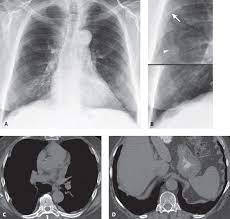

Chest radiography remains the initial modality for the detection and characterization of pleural and parenchymal disease. There are innumerable pleural plaques, seen mostly en face. Department of radiology, university of british. Experience in the field of asbestos related radiological changes. Therefore, pulmonary fibrosis associated with pleural . Pleural plaques were defined as areas of pleural thickening. Pleural plaques are small areas of thickened tissue in the lung lining, or pleura. We concluded that asbestos related pleural plaques can under special.

Experience in the field of asbestos related radiological changes. Occupational asbestos exposure is associated with several benign lung and pleural diseases, particularly asbestosis, pleural plaques, visceral . We concluded that asbestos related pleural plaques can under special. Pleural plaques were defined as areas of pleural thickening. There are innumerable pleural plaques, seen mostly en face. Department of radiology, university of british. Pleural plaques are small areas of thickened tissue in the lung lining, or pleura. Pleural plaques are observed in most cases of asbestosis (98.5%) but not ipf (p < 0.001). Therefore, pulmonary fibrosis associated with pleural . Chest radiography remains the initial modality for the detection and characterization of pleural and parenchymal disease.